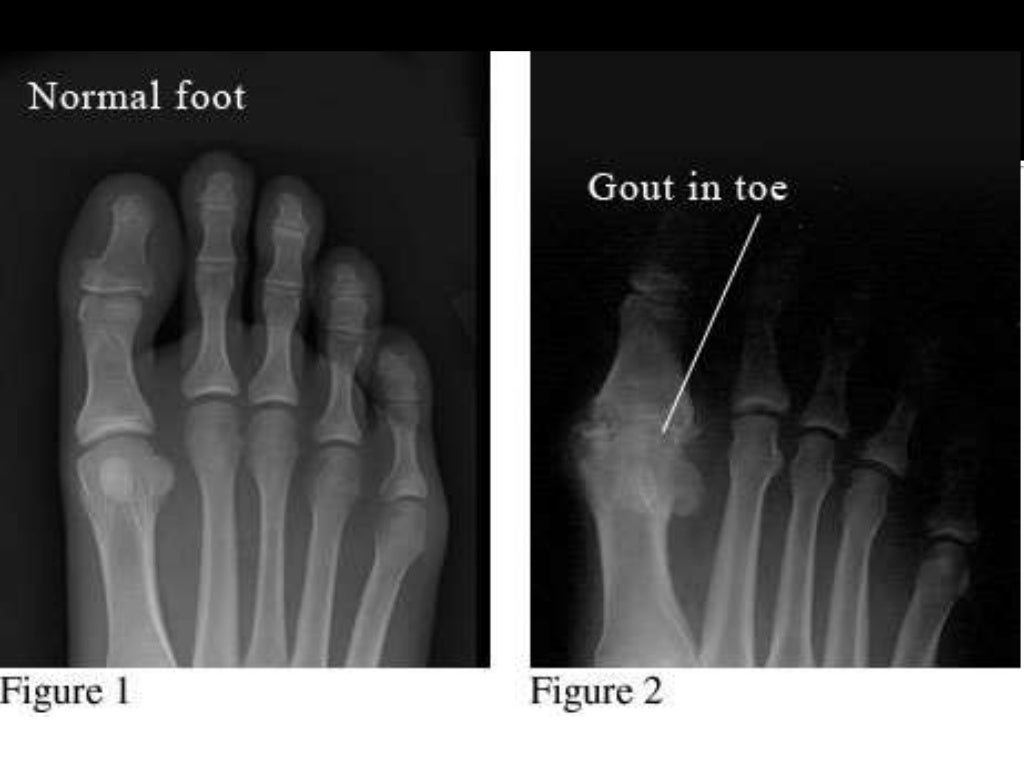

Пфс сустав

Пфс сустав 112 фото